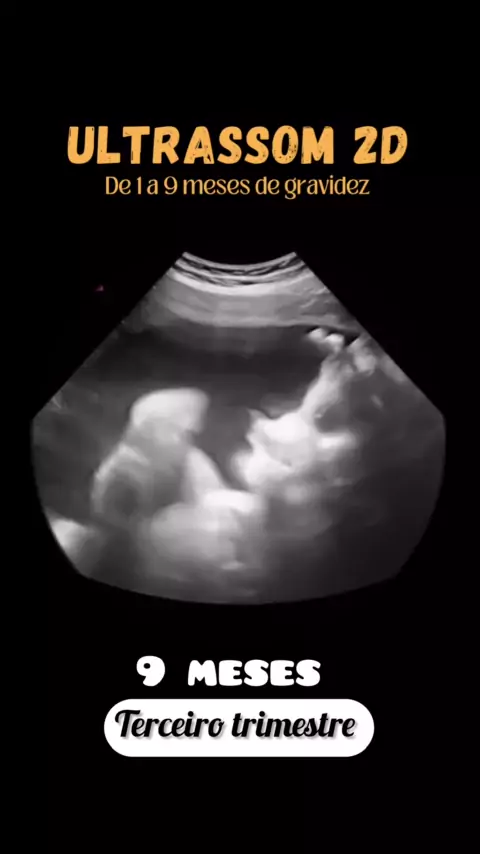

Mamães e Tentantes